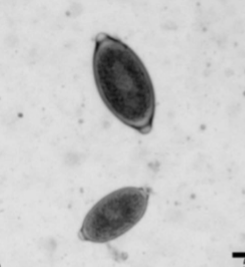

Dioctophyma renale

“giant kidney worm” of dogs, mink, raccoons, and humans

where does Dioctophyma renale live in the body of host

infects the right kidney.

symptoms of Dioctophyma renale

kidney/abdominal pain, enlargement, hematuria, proteinuria, lethargy, weight loss, can destroy entire contents of kidney, just leaving a “shell”

what lifecycle does Dioctophyma renale have

indirect with 2 aquatic intermediate hosts (worm and frog or fish)